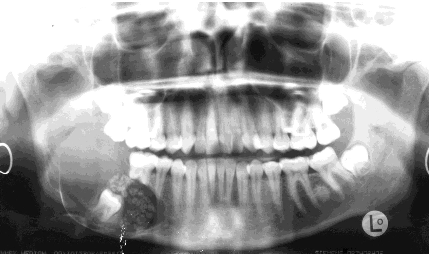

What is this?

An Ameloblastic fibro-odontoma